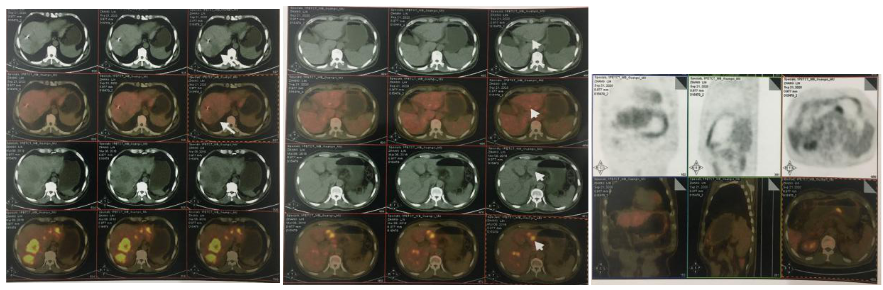

2018-11-14 CT(8周期化疗后):PD?

△基线水平

△治疗后

2018-11-19 PET/CT

胃壁代谢稍增高但未见明确的肿物,肝内低代谢结节考虑转移瘤治疗后活性减低,纵膈及右肺门两个淋巴结代谢增高,考虑转移瘤活性尚存、左侧颞骨局部骨质破坏并代谢增高,考虑转移瘤。